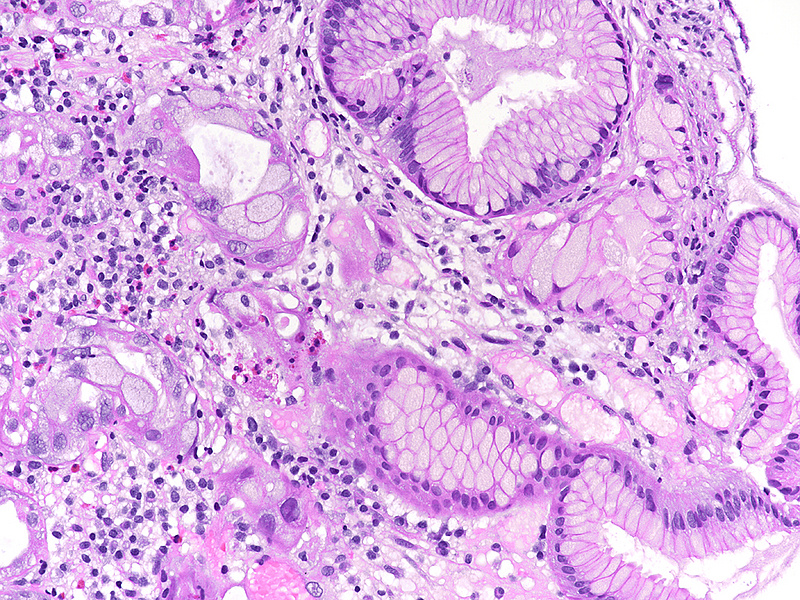

A 41-year-old female with ocular malignant melanoma, metastatic to both lobes of the liver, presented with nausea, vomiting and epigastric pain. Upon endoscopy, a large ulcerated lesion, extending from the corpus to the duodenal bulb, was detected (Panel A). Upon histology, ballooning cells with mild to moderate nuclear atypia were observed within the surface and foveolar epithelium (Panel B-C). Marked nuclear pleomorphism, hyperchromasia and loss of polarity, along with increased cytoplasmic eosinophilia were present within the deep gastric glands (Panel D). Mitotic figures were not seen, and  the  Ki-67 labelling index was low (Panel E). p53 overexpression was noted in the atypical cells, however with  heterogeneous staining, thereby indicating an activated wild-type pattern (Panel F).